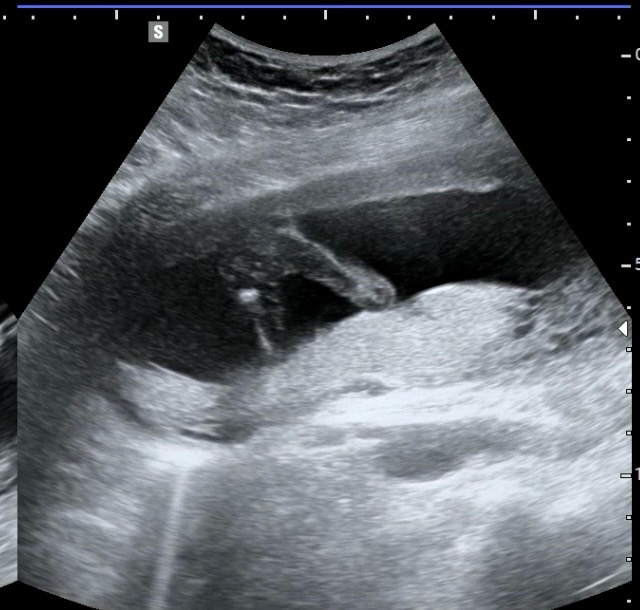

성별 확정 받고 왔네용 🤣

미꾸라지 태몽 꿨다고 남편이 자랑하길래 살짝 기대 했는데ㅋㅋㅋㅋㅋ 너무나 선명하네요 ^ㅁ^ 이로써 자매맘이 되었습니다 연년생 자매라니 겁나게 싸우겠네요 🥹